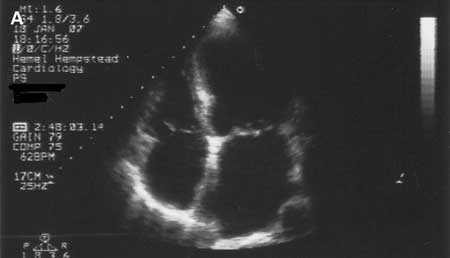

Dilated cardiomyopathy: echocardiogram

Tanejal AK, Wong J, Bayliss J. Antipsychotic-drug-induced dilated cardiomyopathy. BMJ Case Reports. 2009; doi:10.1136/bcr.09.2008.0958